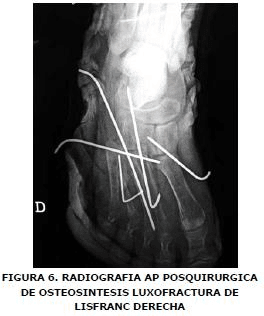

Se aplicó antibioticoterapia biconjugada y manejo de tejidos blandos. Quince días más tarde, se realizó reducción abierta con osteosíntesis definitiva con clavos de Kirschner en luxofractura de pie derecho tipo Lisfranc B2, con desplazamiento lateral. Encontrándose minutas en los metatarsianos (Figuras Nº 5 y Nº 6), en tobillo izquierdo se adelantó reducción abierta mas osteosíntesis con tornillos de esponjosa en superficie articular anterior de tibia distal y con clavo de Steinman se fijó articulación tibioastragalocalcanea, izquierda (Figura Nº 7). La paciente presento escaras sacras con evolución favorable y finalmente salió de alta hospitalaria a los 64 días de ocurrido el trauma.

Se aplicó antibioticoterapia biconjugada y manejo de tejidos blandos. Quince días más tarde, se realizó reducción abierta con osteosíntesis definitiva con clavos de Kirschner en luxofractura de pie derecho tipo Lisfranc B2, con desplazamiento lateral, encontrándose minutas en los metatarsianos (Figuras Nº 5 y Nº 6), en tobillo izquierdo se adelantó reducción abierta mas osteosíntesis con tornillos de esponjosa en superficie articular anterior de tibia distal y con clavo de Steinman se fijó articulación tibioastragalocalcanea, izquierda (Figura Nº 7).

En nuestro caso empleamos una férula con buenos resultados en la protección posoperatoria, colocada luego del procedimiento quirúrgico de reducción abierta mas osteosíntesis con clavos de Kirschner. Otros defienden el manejo con reducción abierta y argumentan, que la descompresión de los compartimentos del pie previene un síndrome compartimental, aunque esto condiciona al paciente a otra intervención para retiro de material. Además existe riesgo de daño articular con rigidez y artrosis (1, 4, 6).